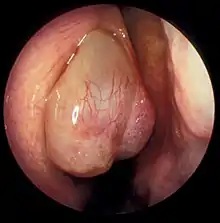

| A nasal polyp | |

Nasal polyps can be seen on physical examination inside of the nose and are often detected during the evaluation of symptoms. On examination, a polyp will appear as a visible mass in the nostril.[5] Some polyps may be seen with anterior rhinoscopy (looking in the nose with a nasal speculum and a light), but frequently, they are farther back in the nose and must be seen by nasal endoscopy.[12] Nasal endoscopy involves passing a small, rigid camera with a light source into the nose. An image is projected onto a screen in the office so the doctor can examine the nasal passages and sinuses in greater detail. The procedure is not generally painful, but the person can be given a spray decongestant and local anesthetic to minimize discomfort.[13]

Attempts have been made to develop scoring systems to determine the severity of nasal polyps. Proposed staging systems take into account the extent of polyps seen on endoscopic exam and the number of sinuses affected on CT imaging. This staging system is only partially validated, but in the future, may be useful for communicating the severity of disease, assessing treatment response, and planning treatment.[6]